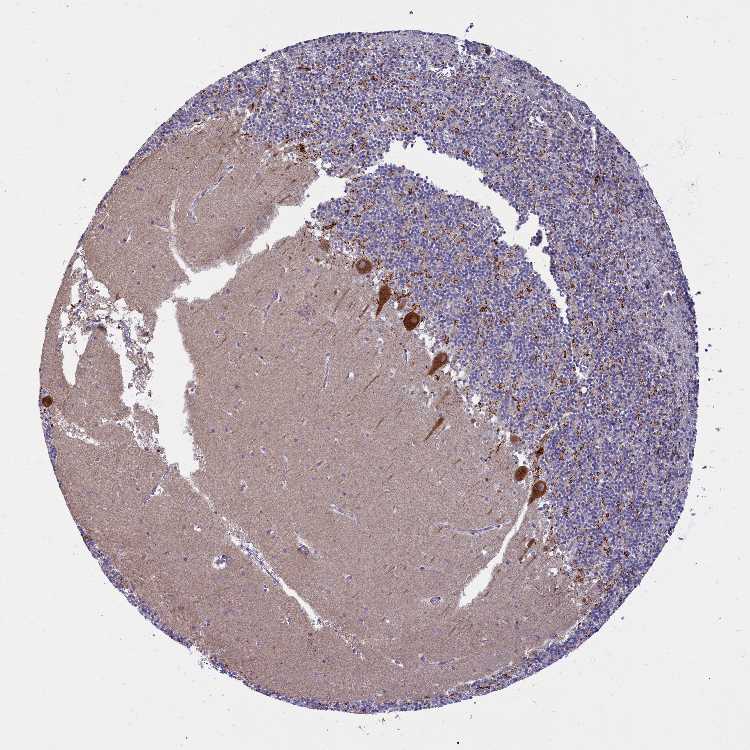

BRAIN CEREBELLUM Show tissue menu

CEREBELLUM - Antibody stainingi

Antibody HPA040770

Bergmann glia - cytoplasm/membrane Not detected

Bergmann glia - nucleus Not detected

GLUC cells - cytoplasm/membrane High

GLUC cells - nucleus Not detected

Purkinje cells - cytoplasm/membrane High

Purkinje cells - dendrites High

Purkinje cells - nucleus Not detected

Granular cells - cytoplasm/membrane Not detected

Granular cells - nucleus Not detected

Molecular layer - neuropil Not detected

Molecular layer cells - cytoplasm/membrane Not detected

Molecular layer cells - nucleus Not detected

Processes in granular layer High

Processes in molecular layer Not detected

Processes in white matter High

Synaptic glomeruli - capsule Not detected

Synaptic glomeruli - core High

White matter cells - cytoplasm/membrane High

White matter cells - nucleus Not detected